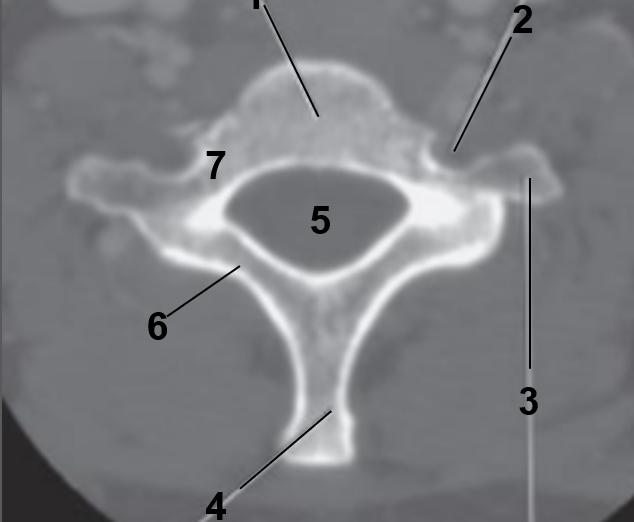

1

Body of of C7

2

Transverse foramen

3

Transverse process

4

Spinous Process

5

Vertebral Foramen

6

Lamina

7

Pedicle